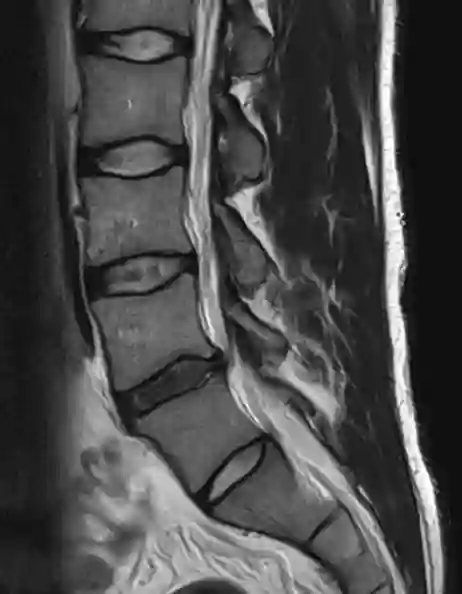

In der MRT Bildgebung zeigt sich eine "Black Disc" mit einem verringerten Signal in der T2 Bildgebung[^1] [^2].

Darstellung des Black Disc Phänomens in einer sagittalen T2 Sequenz der lumbalen Wirbelsäule.